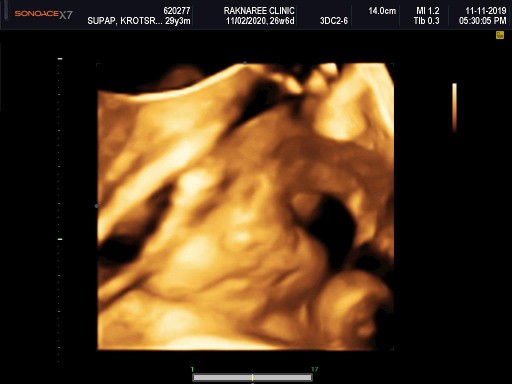

11กุมภา63 จ้า เพศชายจ้า